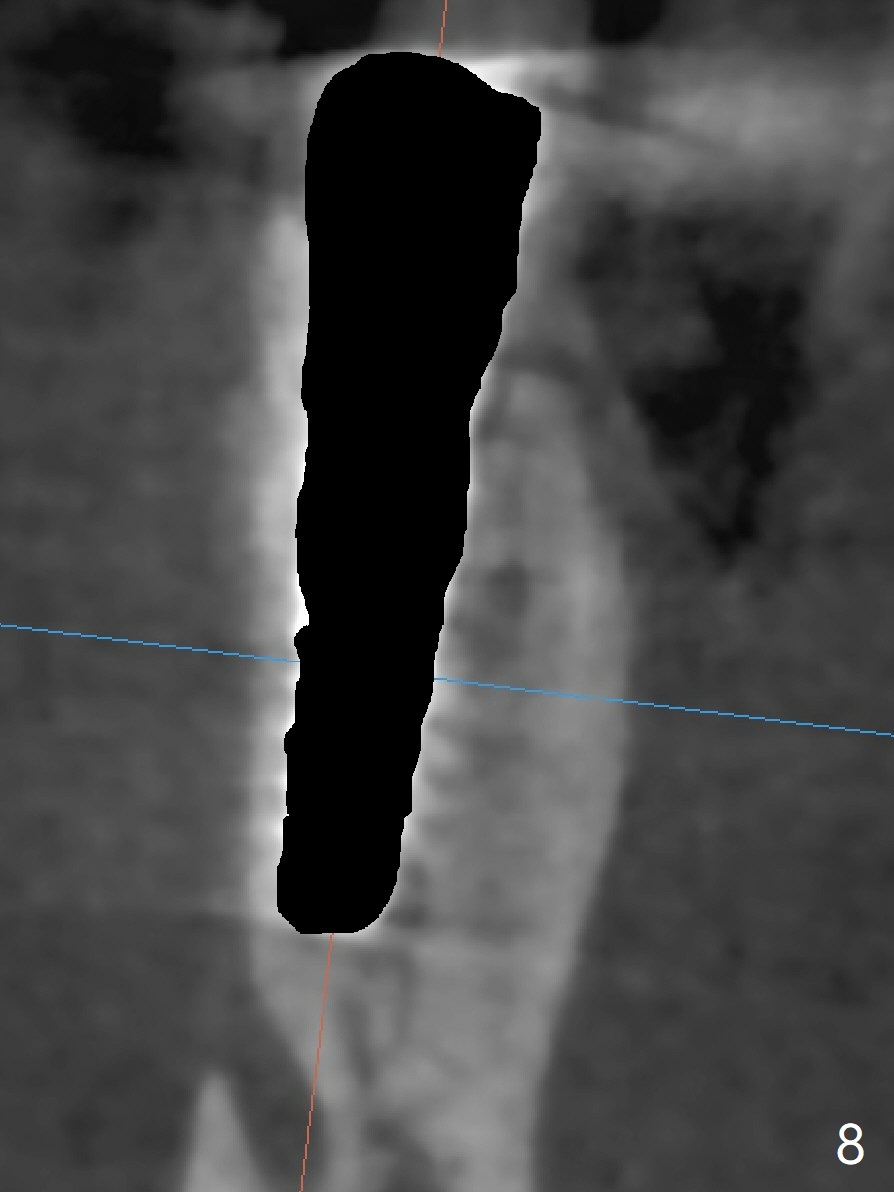

The tooth #29 has mild persistent pain radiating to the temple with mild percussion and mobility I 4.5 months post apicoectomy; the buccal recession is noticeable (Fig.1). Granulation tissue and bone graft are attached to the resected apex of the extracted tooth (Fig.2 <). The initial osteotomy with 1.5 mm drill is distal (Fig.3). After position adjustment with difficulty because of hard bone, osteotomy is finished with 2.8 and 3.2 mm Magic Drills (Fig.4). Following final drill, a 3.5x11 mm IBS implant is placed with insertion torque of 45 Ncm. With placement of a 4.5x4(4) mm abutment, Vanilla graft is placed in the buccal gap (Fig.5). Immediately postop CT shows that the implant is buccally placed (Fig.6,7 B). In fact after extraction (Fig.8), the initial osteotomy should start obliquely and as coronal and lingual as possible (Fig.9 red line). Following the initial penetration, the osteotomy should be straightened (Fig.10) so that the implant could be placed lingually (Fig11 green) to reduce buccal thread exposure. In fact there is also buccal thread exposure at #30 (Fig.12). The bone loss at #29 and 30 is minimal 4 months postop (#29, Fig.13 *)) and severe with periimplantitis at #29 one year post cementation (Fig.14). Incision will be made to exposure buccal threads of #29 and 30. If threads are within bone boundary, bone graft will be done with sticky bone after Titanium brush. If not, remove implant threads and bone graft. The worst scenario will be handled with implant removal (trephine bur 4/5 mm), either with bone graft or implant being placed lingually (IBS 3x11 mm 2-piece, to be buried, if needed (Fig.15)). Take preop photos to show #29 and 30 buccal recession and gingival erythema.